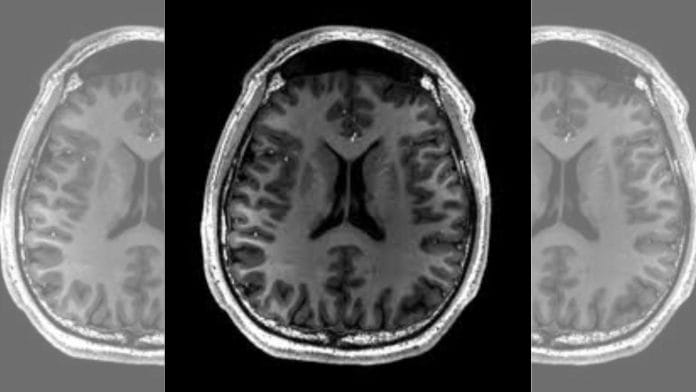

A stroke, also known as a brain attack, occurs when blood supply to a part of the brain gets blocked (ischemic stroke) or when a blood vessel in the brain bursts (haemorrhagic stroke).

In either situation, parts of the brain become damaged or die. This can result in lasting brain damage, long-term disability, or death.

The device being tested in the GRASSROOT trial is designed for mechanical thrombectomy, a procedure for removing clots from a blood vessel. Senior neurologists at AIIMS Delhi said that at least 3.75 lakh patients can benefit annually from the interventional stroke treatment.

It is a procedure that removes a blood clot from an artery in the brain to treat an acute ischemic stroke. As part of the procedure, a catheter is inserted into an artery, usually in the groin, and guided to the clot.